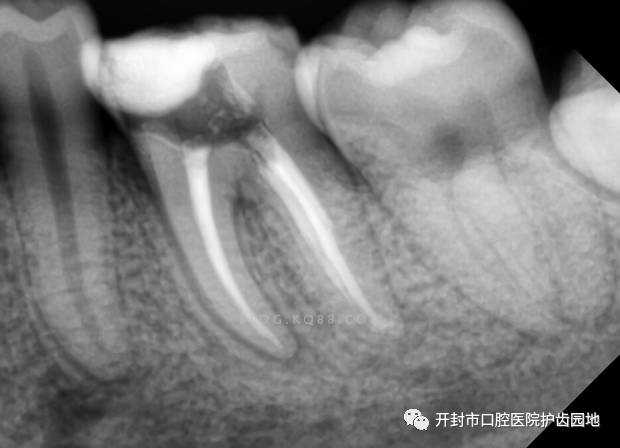

拍X射线照片,确定患处结构和手术方案。 施以局部麻醉。 钻开牙齿,去除腐坏的牙体组织。 打开牙髓腔,取出牙髓组织,并预备成形根管。 用消毒液(例如氯酸钠溶液)冲洗根管内部后,再用专门的材料充填根管,保证长期处于无菌状态。 填补牙齿的钻洞,或安装牙冠。 最后我们来看一看根管治疗后的X射线照片,是不是很完美。 牙体牙髓科科 牙体牙髓科是我市口腔医院主要临床科室之一,开封市医学重点专科。拥有超声综合治疗仪、镍钛根管预备和热牙胶根管充填器械、根管长度测量仪、牙髓活力测试仪等技术设备,牙体充填修复材料应用与国内前沿同步。精于龋病、牙髓病和根尖周病的诊治,年轻恒牙根尖诱导术、牙本质过敏症、牙外伤的诊治,前牙无髓变色牙的内漂白治疗。开展的牙髓病无痛治疗术、ProTaper预备根管和热牙胶充填术等。 牙体牙髓病科 张运祥 文中图片来源于网络 张运祥 市口腔医院牙体牙髓病科主任,主治医师,郑大口腔医学院学士学位。擅长龋病、牙髓病、根尖周病等治疗,熟练开展国际先进的“镍钛机动根管预备”、“热牙胶三维根管充填”等技术。